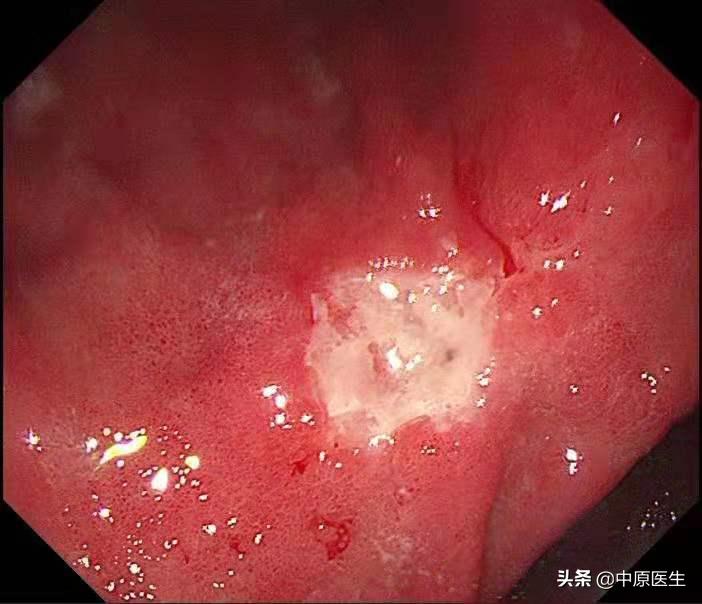

胃镜安排在上周五,*操我**作胃镜,顺利通过食管,准确到达了胃内,果然在胃角中间的地方,发现了一个溃疡,我的心头一紧,这可不像是早期胃癌呀!

通常,在胃镜检查时发现溃疡病变,需要做良恶性鉴别,内镜下鉴别良性和恶性溃疡(也就是通常说的胃癌)需要从以下几个方面考虑,第一、病变的大小,大的溃疡恶性的可能性大。第二、形状,恶性溃疡往往形状不规则;第三、恶性溃疡的底部往往凹凸不平;第四、恶性溃疡表面的苔往往污秽(很脏);第五、恶性溃疡的边缘多伴有结节样隆起,反之,则良性可能大。

这个患者的溃疡多发,不算太大,并且表面的苔很干净,底部也算平坦,尤其是新发现的两个溃疡,从这几个条件来看,似乎良性可能性大。但是,我还是不放心。我现在只是用了白光检查,为什么不选择窄带光,放大检查?虽然麻烦一点,但是,可以看到更多细节!于是,我打开NBI模式,并且使用变焦(俗称放大,可以达到和显微镜下看类似的效果),再仔细地对每一处病变进行了观察,结果竟然发现,虽然范围很小,尤其是胃窦处的溃疡,不超过2个毫米的范围内我都发现了腺管缺失和血管异常扩张的地方,这往往提示病变有可能已经癌变,在放大镜的引导下,我对病变进行了精准活检。